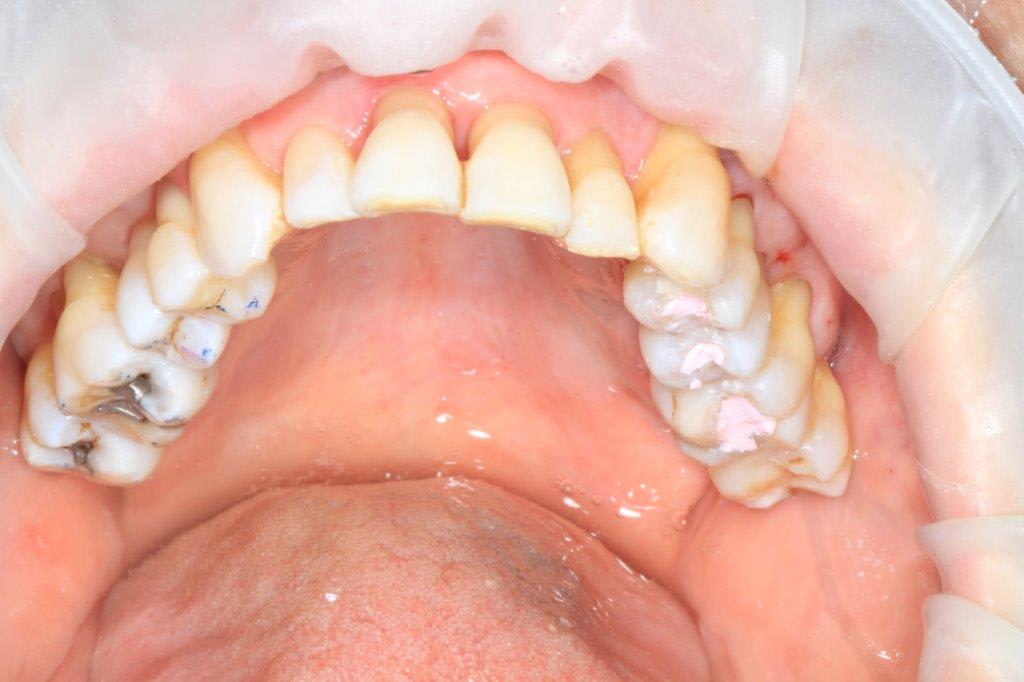

non, pour les wax-up, ce n'est pas par addition, je meule les dents avant, c'est en gros une simulation de ce que je peux faire en bouche, en particulier de savoir ce que je pourrais ou non garder vivant, fonction de ce que j'enlève en volume et en axe.

et pour ce cas, pas d'augmentation (à priori) de la Dv, donc diminution, de la hauteur des incisives max. et mand., afin d'essayer de retrouver une ligne de sourire correcte ( qui soit agréable pour la patiente et surtout moins nocive).

Pour les postérieures, je n'ai touché à rien , à part légèrement 24 et 14, donc je referai des empreintes un peu plus tranquillement (j'avais peur, d'avoir quelques dents dans l'empreinte la première fois) et je pourrais enregistrer les différents paramètre de façon plus sérieuse.

petit boulot de ce jour, "coronoplastie de sauvage", afin d'essayer de supprimer les contacts nocifs... ensuite endo 24/25/26.

J aime bien ton meulage de 14,15 faces palatines pour la laisser partir àgauche .

Par contre comme je te l ai dit , simultanément j aurais aligné les crêtes proximales.

surtout dans des cas comme celui là où il y a des mylolyses bilatérales et une double occlusion.

Le fait de ne pas supprimer les décalages de crête, alors que tu lui a enlevé son calage ant , et va faire du bruxisme centré ( serrage ') de compensation sur les crêtes les plus saillantes n ayant plus d engrenement suffisamment stable .

Au't chose , tu as diminué le recouvrement ant , c est bien , mais ce qui n empêche qu il faudrait biseauter les bords livres des incisives du bas et du haut .

Bref on voit mieux sur ces photos que ce sera le haut qu il faudra couronner en fonction du bas qui lui n'est pas dégueulasse .